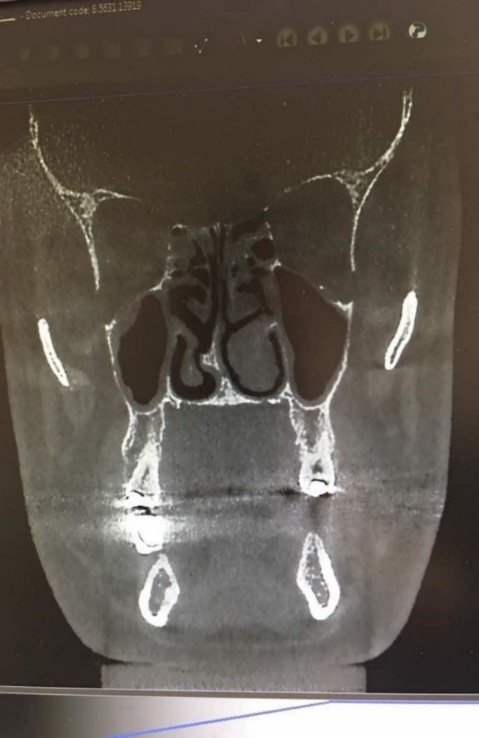

Investigation of the frequency of nasal septum deviation in males showed that 33.3% of the deviations were type I, 13.7% were type II, 1.96% were type IV, 17.65% were type V, 1.96% were type VI, and 5.88% were type VII. In females, 26.53% were type I, 14.29% were type II, 2.04% were type III, 8.16% were type IV, 18.37% were type V, 4.08% were type VI, and 2.04% were type VII (Table 2 and Figure 1).

Figure 1. Spore-shaped septal deviation.